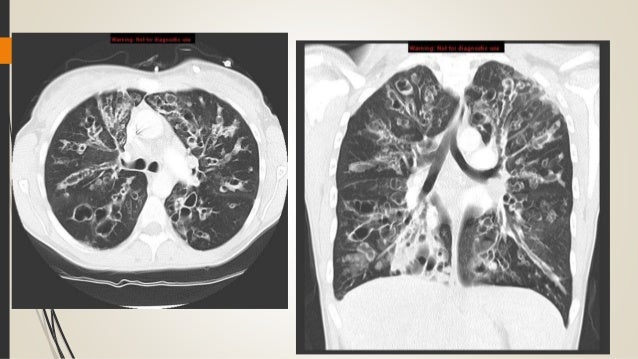

Cystic Fibrosis Ct Scan Axial View Stock Photo Alamy

Cystic Fibrosis Ct Scan Axial View Stock Photo Alamy from c8.alamy.com